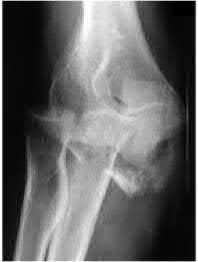

A 34-year-old male falls from a roof and sustains a right elbow dislocation that is closed reduced in the emergency room. An AP radiograph is shown in Figure A. This injury pattern is at highest risk for which of the following?

Anteromedial coronoid facet fracture and LCL injury following an elbow dislocation is commonly associated with varus posteromedial rotatory instability. Varus and posteromedial rotation force on the forearm results in rupture of the LCL from its humeral origin. As the LCL ruptures, the medial coronoid process is fractured as it impacts against and under the medial trochlea. Fracture involvement of the sublime tubercle, where the MCL attaches, can lead to more instability. Ulnar neuropathy can be seen following this injury pattern but AIN and PIN nerve palsy do not commonly characterize this injury pattern.

The review article by O'Driscoll highlights key points in diagnosis and management of capitellum, distal humerus, coronoid, and terrible triad injuries.

The article by Doornberg and Ring is a Level 4 study of 18 patients that sustained varus posteromedial rotational injuries resulting in anteromedial facet coronoid fractures. They found that lack of fixation at injury or malunion of the anteromedial facet were significant predictors of suboptimal functional outcome and development of arthrosis.

The anteromedial facet is highlighted in yellow as displayed in Illustration A. Illustration B depicts the lateral collateral ligament injury also evident during

varus stress fluroscopic examination, due to tension failure of the LCL off its humeral origin during the various mechanism.